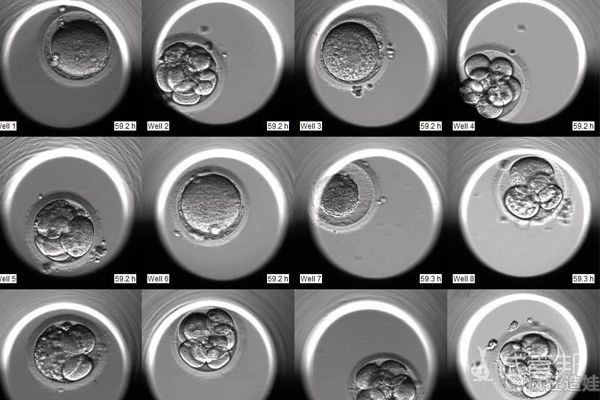

促排方案包括了打促排针、保卵针等等,生殖专家会观察卵泡发育情况,并根据情况调整药剂剂量,在卵泡发育良好的情况下,可能能有很多个优质卵泡。通常取卵个数,取决于女性的卵巢情况,取卵结果影响的是最后的胚胎数量。取卵后的第3-5天,医院会将培育出的胚胎数量通知患者,胚胎数量越多,就可以从中挑选优质胚胎进行移植,成功怀孕的可能性就会越大。